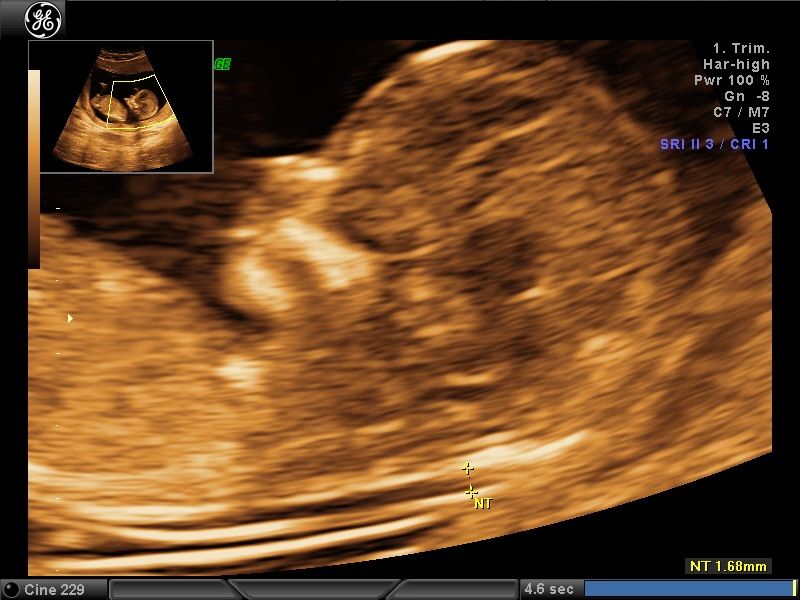

Wykonuję tam około 600 badań „I trymestru ciąży” rocznie, co daje łącznie około 1200 badań z „II trymestrem ciąży” włącznie. Od 15 lat w swoim gabinecie również wykonuję badania prenatalne I, II i III trymestru ciąży w znacznej ilości. To umożliwia mi osiągnięcie doskonałych wyników w diagnostyce tych badań, co stawia mnie w czołówce specjalistów diagnostyki prenatalnej.

Większość swojej kariery zawodowej spędziłem na sali porodowej oraz patologii ciąży. Aktualnie pracuję na sali porodowej. Mam 15-letnie doświadczenie w diagnostyce prenatalnej poparte dużą ilością przebadanych pacjentek i posiadam najszerszy wachlarz certyfikatów z zakresu ultrasonografii płodowej. Corocznie uczestniczę w szkoleniach i kursach ultrasonograficznych.

Moje kwalifikacje podparte są 1 wymaganym i 3 dodatkowymi certyfikatami Fetal Medicine Foundation (FMF) tj. certyfikat wymagany NT przezierność karkowa oraz certyfikaty dodatkowe DV, TR, NB.

- diagnostyka prenatalna I,II i III trymestru ciąży z przepływami dopplerowskimi, testem podwójnym (PAPPA i B-HCG), oznaczanie DNA płodowego NIPTY, testy SANCO, NIFTY, VERACITY